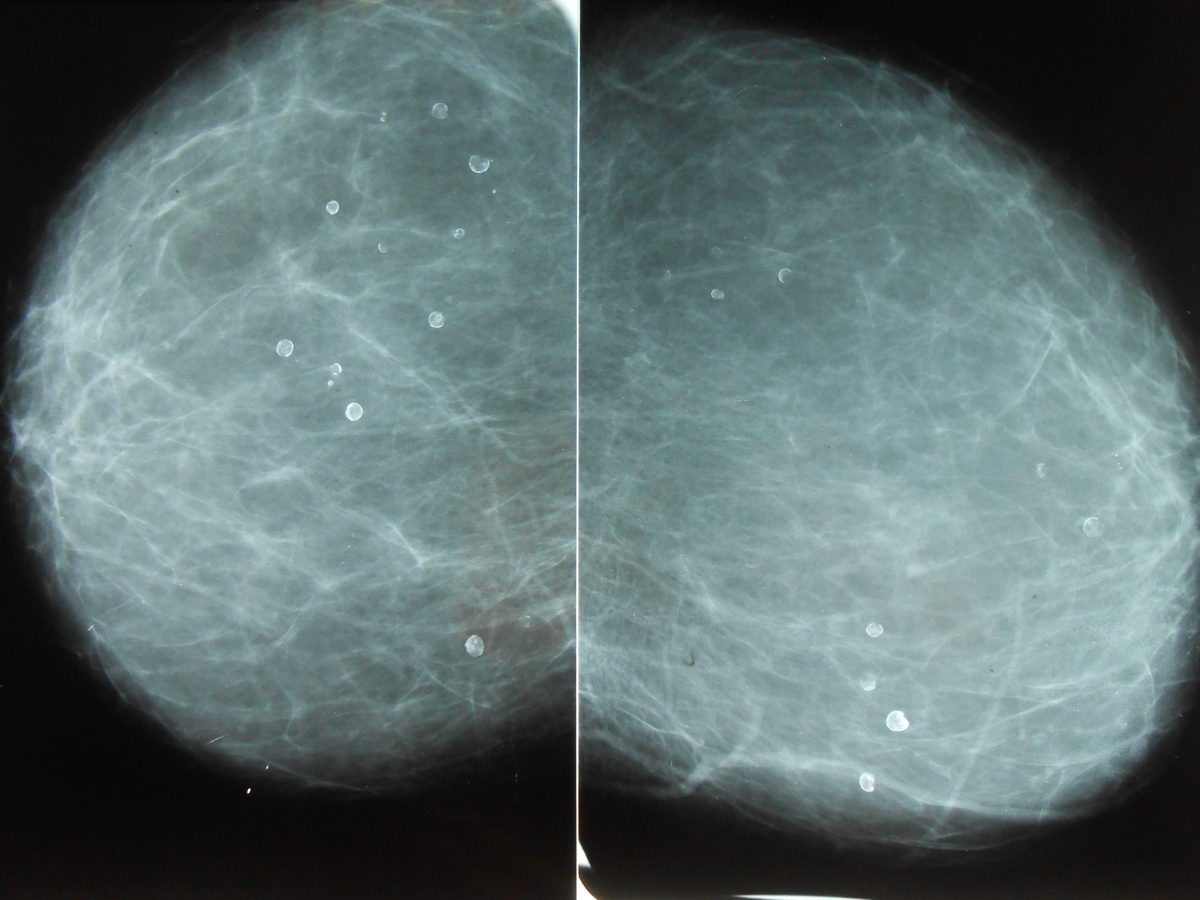

Фиброаденома молочной железы - доброкачественное образование, которое часто встречается у женщин. Оно может быть обнаружено при помощи различных методов диагностики, включая маммографию. Ниже представлены фотографии, помогающие понять, как выглядит данное заболевание.

Маммограмма кальцинаты визуализируются

Кальцинаты маммограмма

Маммография и ее роль в диагностике фиброаденомы молочной железы

Маммография - это рентгенологическое исследование молочных желез. Оно позволяет выявить различные изменения в тканях, включая фиброаденому. На маммограммах можно увидеть структурные особенности опухоли и отследить ее динамику во времени.